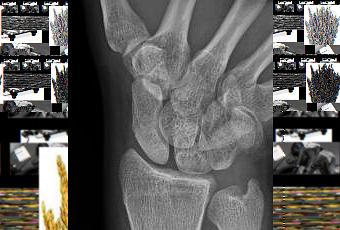

Las enfermedades de los huesos, en muchos casos, pueden tener origen en un problema circulatorio. Una de estas enfermedades es la osteonecrosis. Se trata de un problema de salud que ataca directamente al sistema óseo y se caracteriza por la pérdida del suministro de sangre que reciben los mismos. Al perder su irrigación sanguínea, los huesos con osteonecrosis terminan destruyéndose y, tarde o temprano, pueden colapsar.

Los primeros síntomas que sienten aquellos que sufren de osteonecrosis es un fuerte dolor articular y sensación de debilidad en los huesos. La osteonecrosis siempre viene aparejada de artritis. Esta enfermedad ósea puede afectar a uno o a varios huesos de forma simultánea. Uno de los huesos que se suele ver implicado en la osteonecrosis es el que está ubicado en la parte superior de la pierna. Otros lugares comunes en los que puede aparecer osteonecrosis son los brazos, los hombros, las rodillas y los tobillos.

Hay que tener en cuenta que esta enfermedad de los huesos puede afectar tanto a hombres como a mujeres y se puede presentar en personas de entre 30 y 50 años. Algunos de los factores de riesgo que pueden predisponer a una persona a sufrir de osteonecrosis son el alcoholismo, las lesiones articulares de tipo crónico, los tratamientos con esteroides prolongados en el tiempo y la presencia de ciertos tipos de cáncer o de artritis. Para mejorar el estado de salud después de una osteonecrosis lo que se recomienda son medicamentos específicos, estimulación eléctrica y cirugía. En casos de osteonecrosis puede ser necesario el uso ocasional de muletas para proteger al frágil sistema óseo y, casi siempre, se ofrecen indicaciones detalladas sobre las actividades que habría que limitar para evitar un empeoramiento de esta condición (por ejemplo, no correr, cargar pesos o hacer actividades con demasiada exigencia).